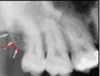

1

Not at all

2

3